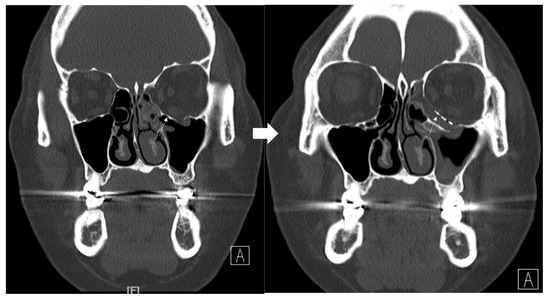

An 8-year-old boy came to our emergency room with nausea, vomiting, bradycardia, and lethargy following a left eyeball trauma hit by a baseball. The patient complained of severe pain and discomfort with eyeball movement (Figure 1). We surgically approached the inferomedial orbital wall fracture on the same day of the trauma. After the subciliary incision, the fracture was exposed. The titanium-reinforced porous polyethylene (TR-PPE) plate was placed on the fracture site using a single screw at the inferior orbital rim (Figure 2). The oculocardiac reflex was entirely gone immediately after surgery. The patient was discharged on postoperative day 2 with significantly improved pain and discomfort.

Figure 1. Case 1. Preoperative facial CT scan (coronal view) of the 8-year-old male patient with left inferomedial orbital wall fracture. The fracture sites were designated with white arrows.

Figure 2. Case 1. Follow up facial CT finding (coronal view) of the same patient. The titanium-reinforced porous polyethylene (TR-PPE) plate placed on the inferomedial wall using a single screw at the inferior orbital rim. (White arrow).